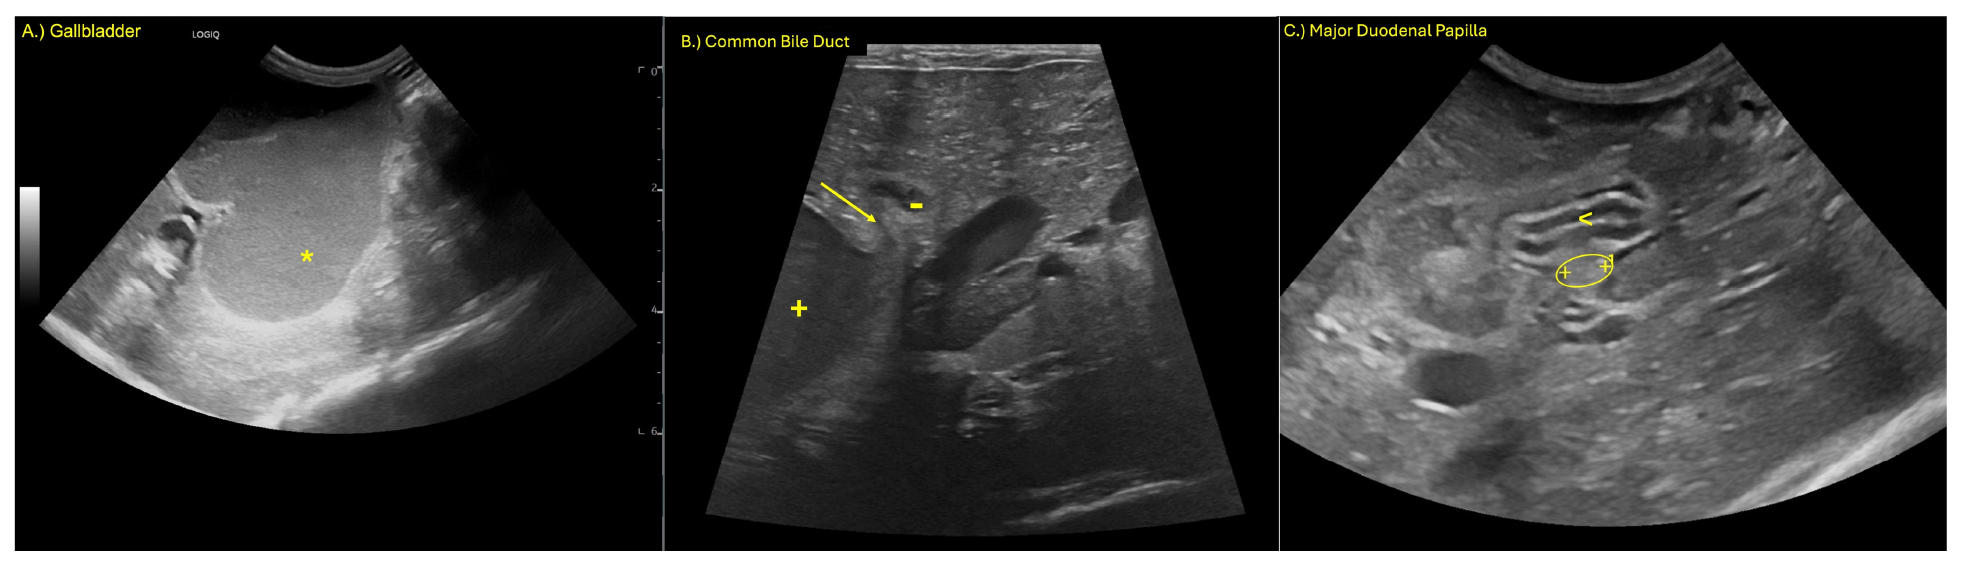

凝血功能显示部分凝血活酶时间增加至参考值的四倍(66.7秒 [11.9–16.2]),D-二聚体水平也升高。总体而言,检查结果未见明显变化或仅有轻度进展,同时观察到十二指肠乳头增厚(下图)。

↑ (A) 胆囊(*)显著扩张,(B) 肝内胆管扩张(+,边界以1和+标记),(C) 十二指肠乳头增厚(椭圆形,乳头边界以+、1和2标记)。